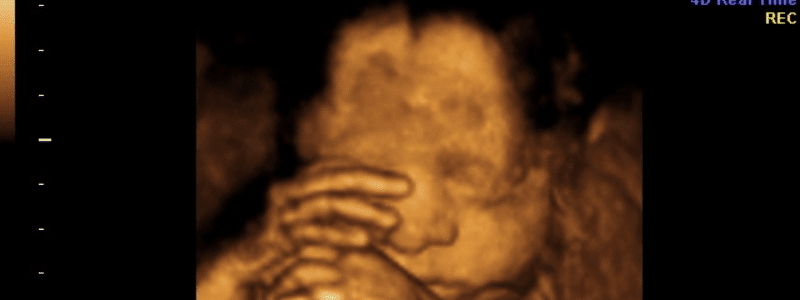

My research project this summer focuses on the effects of e-cigarettes on prenatal development, which is not widely researched. My project is a pilot study comparing the upper facial movement of foetuses exposed to maternal use of e-cigarettes, cigarettes, and those with no exposure.

The use of cigarettes during pregnancy is advised against due to the negative implications on fetal development, such as reduced pre and postnatal growth (Vielwerth et al., 2007). Stopping smoking can be challenging due to cigarettes containing the addictive chemical nicotine (NHS, 2022). Recommendations are given to use nicotine alternatives, one being e-cigarettes, a suggested less harmful alternative, facilitating the smoke-free provision of nicotine (NHS, 2020). However, there is increasing academic concern about this. Research has concluded that both fetal e-cigarette and cigarette exposure during pregnancy impact postnatal birth outcomes and motor maturity compared to non-exposed fetuses with high similarities (Froggatt et al., 2020). Reissland et al. (2015) also concluded that the prenatal fetal movement profile differs between those exposed to maternal cigarette use and those without. Due to the postnatal implication of prenatal cigarette and e-cigarette exposure aligning, it is suggested that prenatal fetal movement should also match. This project sets out to investigate whether this can be evidenced; it will act as a pilot study comparing fetal facial movements between those exposed to maternal use of e-cigarettes and cigarettes and those with no exposure. From this, further research can be conducted to identify whether the findings are observable in a larger sample size.

Training will be completed to gain proficiency at completing fetal ultrasound movement coding. This will involve learning how to code using the Fetal Observable Movement System (FOMS) (Reissland et al., 2016). The upper facial movement of 30 4D ultrasound scans for the three study groups will then be coded. Five will coded for each group, at both 32 weeks and 36 weeks. The results for each will be compared alongside codes of the lower facial movements for each scan, already completed by Dr Suzanne Froggatt-Gray. Statistical analysis will identify any significant variation between the three exposure groups. These findings will provide a basis for future coding and analysis. To conclude, research will be conducted to understand the potential implications the findings obtained may have on healthcare policymaking regarding maternal use of cigarettes and e-cigarettes.